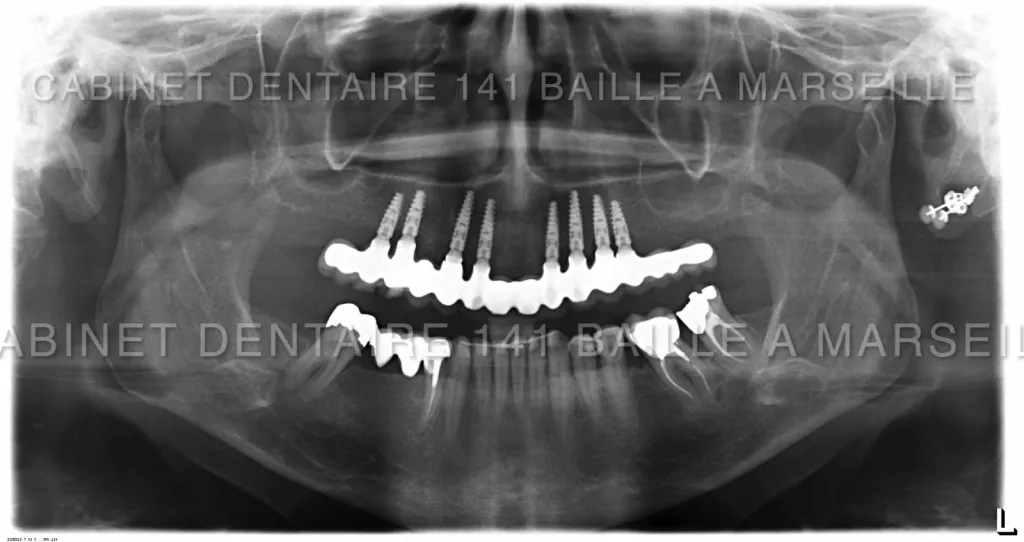

Il peut arriver qu'un patient soit obligé de remplacer toutes ses dents par des implants  dans certains cas de maladies de gencives très agressives qui entrainent une destruction de l'os support des dents .

Avant l'implantologie,ces patients n'avaient pas d'autres solutions que le port d'un appareil dentaire amovible aussi appelé par le grand public "dentier".Ces patients étaient amoindris psychologiquement car ils ressentaient le port de cette Prothèse comme un signe précoce de sénilité.De plus les appareils dentaires s'avéraient astreignants à l'usage .Ces appareils engendraient aussi un affaissement osseux rapide car l'os sous l'effet des pressions masticatoires se résorbait.

De nos jours il est possible pour ces patients d'avoir recours à des techniques implantaires appelées implantation complète en général effectuées dans la meme journée .On appelle cette technique la technique d'implantation complète avec mise en charge immédiate (MCI).

8. Fabrication et fixation des couronnes : Les couronnes dentaires personnalisées seront fabriquées en laboratoire et fixées sur les piliers.

Ces techniques necessitent toutefois un chirurgien implantologiste qualifié et formé à ces techniques de mise en charge immédiate,d'un plateau technique complet avec bloc opératoire stérile ,prothésiste,et personnel d'assistance chirurgical qualifié.